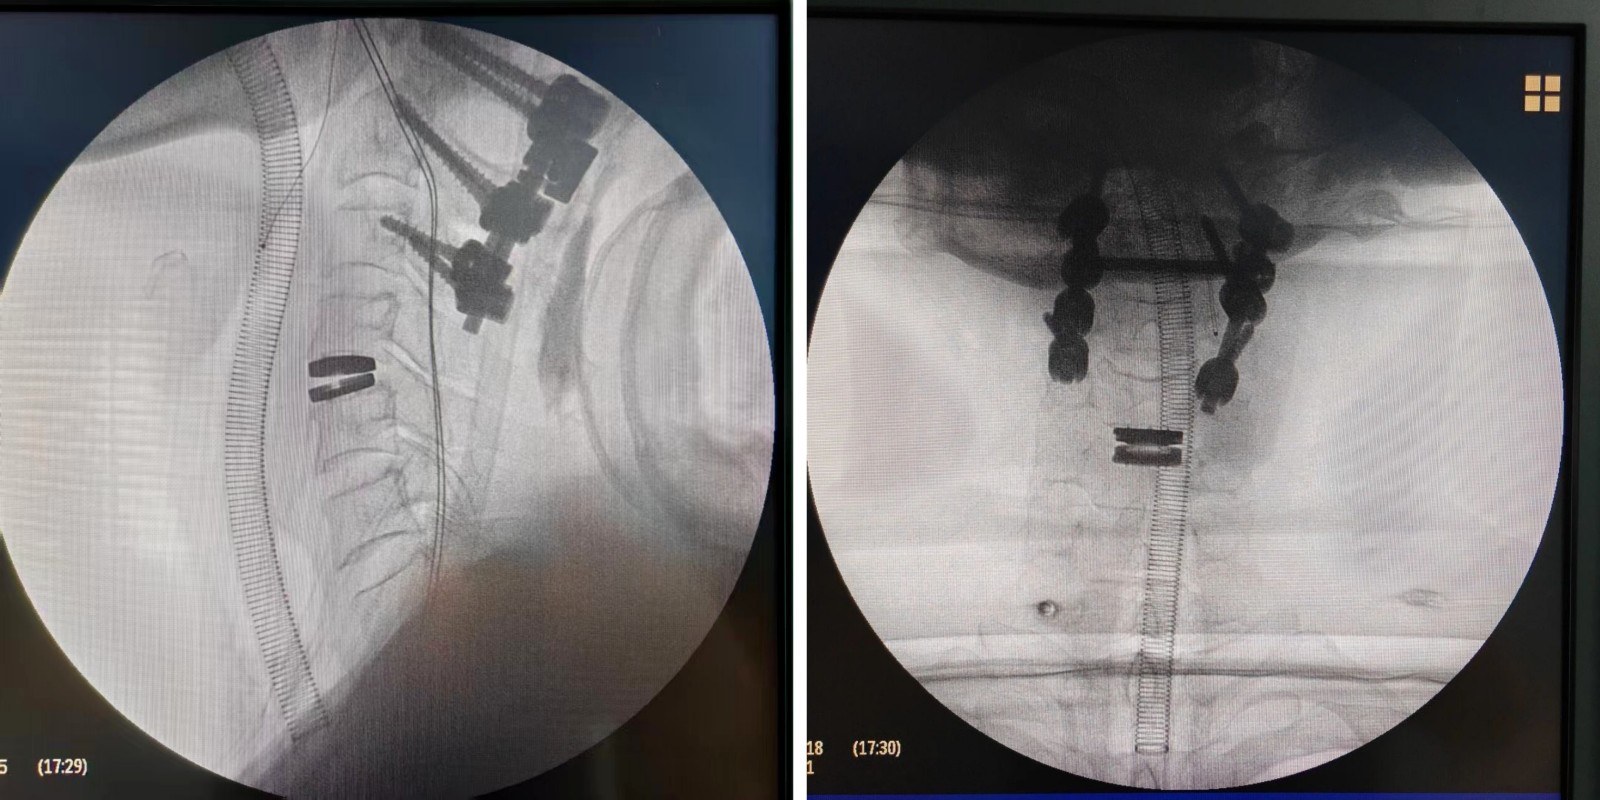

近日,上饶市人民医院骨科吴国保主任团队成功为一名颈椎外伤患者实施“人工颈椎间盘置换术”。该患者因外伤导致枢椎粉碎性骨折伴脱位、颈椎间盘破裂、股骨颈骨折等多发伤入院。经多学科联合评估与周密准备,吴国保主任团队联合麻醉科、重症医学科等专家,先后为一期完成C1、C2、C3切开复位内固定术的患者,顺利开展了二期手术——即上饶市首例人工颈椎间盘置换术。

该手术在保障颈椎即刻稳定的基础上,最大限度保留了患者正常的颈椎活动功能。术中融合精准微创与动态稳定理念,在彻底解除神经压迫的同时,实现颈椎的灵活与稳定兼得,标志着上饶市人民医院在颈椎外科治疗领域迈上新台阶。